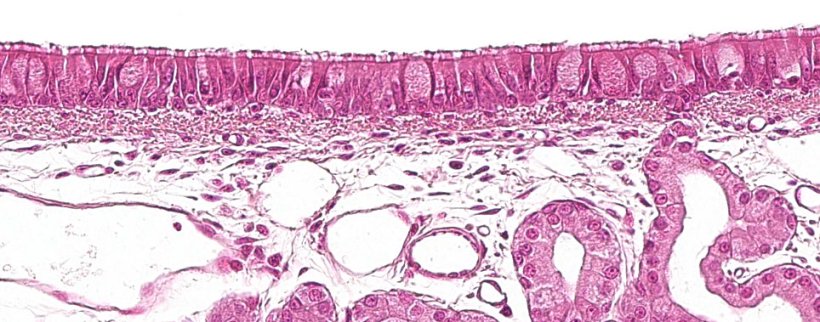

呼吸系统的第一部分,即传导区或呼吸区,从鼻腔一直延伸到细支气管的最后分支,还包括与鼻腔、鼻咽和喉部相连的鼻窦和副鼻窦。所有这些管状结构都是有假复层纤毛柱状上皮的杯状细胞(图1),杯状细胞是负责呼吸道粘膜的主要防御系统之一,即粘膜纤毛系统。该系统由呼吸道上皮细胞的纤毛、杯状细胞的分泌物和呼吸道粘膜下的浆液性腺体组成。它们的主要功能是消除通过吸入空气进入的微粒。腺体在纤毛之间分泌一种清澈、低粘度、富含蛋白质的液体,形成一种促进纤毛向上运动的介质。杯状细胞分泌的粘液沉积在纤毛上,粘附吸入的颗粒。纤毛的向上运动将粘液推向上呼吸道;粘液随后可被吞咽并进入消化道,在消化道被消化,或通过口腔和/或鼻腔排出。导致纤毛损伤的支原体、引起上皮细胞破坏的猪流感或呼吸道冠状病毒等病原体,通过破坏这些防御系统而发挥致病作用。